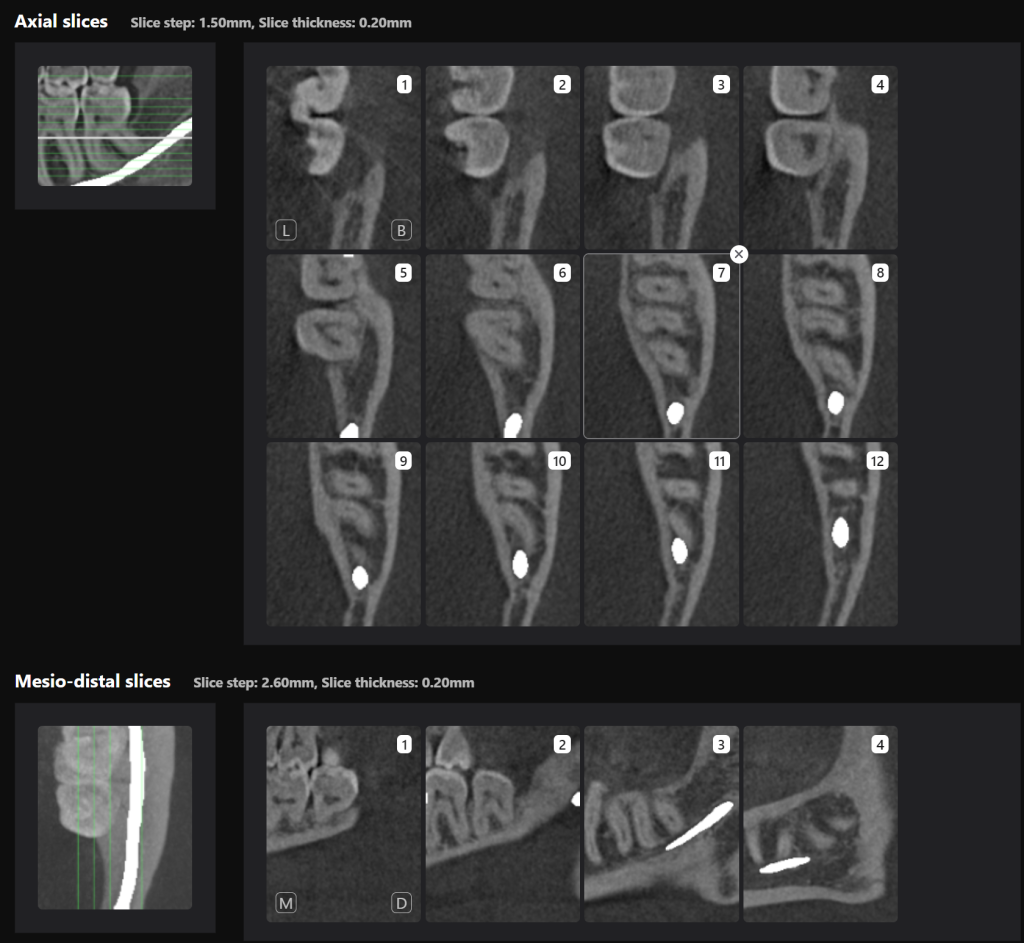

“Third Molar Report” created by Diagnocat AI, is a tool which provides accurate tracing of the mandibular canal

And creating an optimal 3D visualization which helps the clinician to determine the distance to the mandibular canal